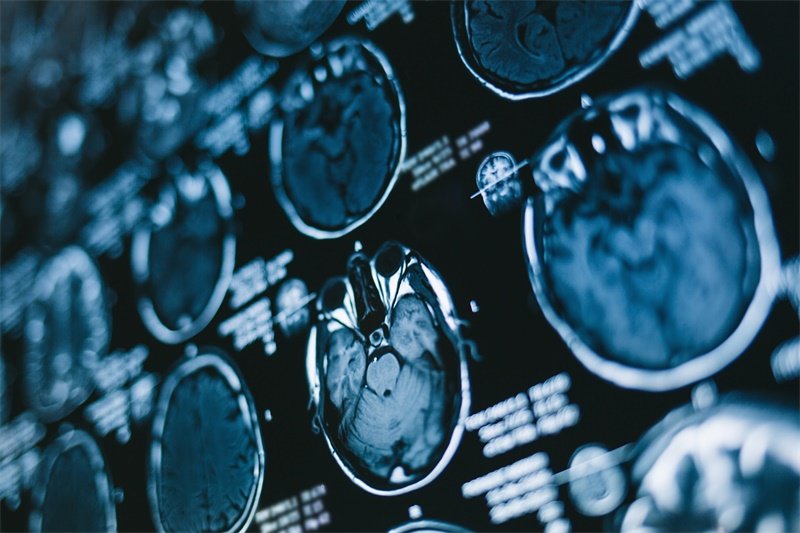

磁共振成像(MRI):能够清晰显示垂体及其周围结构,帮助医生判断肿块的性质、大小及其对周围结构的影响。